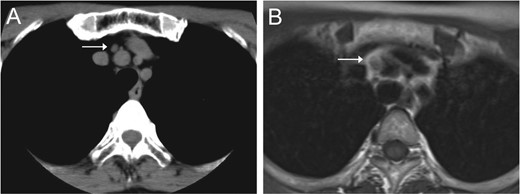

Chest CT (A) and MRI (B) revealed a mediastinal nodule adjoining the BCA.